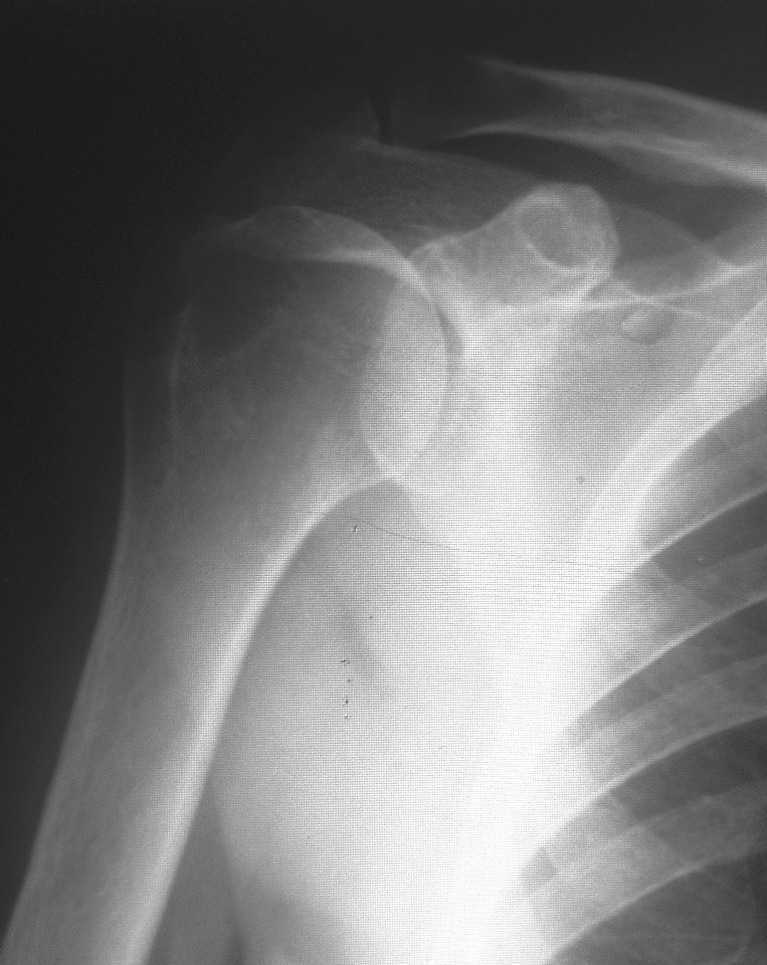

По вашей просьбе размещаю снимок 2003г.

Уважаемые коллеги! Поздравляю всех с наступившим Новым Годом, наступающим праздником Светлого Рождества Спасителя, и прошу помощи в виде ваших комментариев по представленному мною рентгеновского снимка правого плеча. Женщина, 1959 г.р.. Жалоб на функцию правого плечевого сустава не предъявляет, движения в полном объеме, активные и пассивные без ограничений и боли. Меня смущает на данном снимки состояние головки.Сам снимок был проведен с целью контроля состояния сустава, так как больная в 2003 году проходила у меня лечение по поводу правостороннего осифицирующего тендинита надостной мышцы. Если потребуются снимки 2003г. скажите и я размещу.

Меня смущает на представленном снимке <просветление> в области бугра и головки плеча. Или это только мои необоснованные сомнения?

"Меня смущает на представленном снимке "просветление" в области бугра и головки плеча. Или это только мои необоснованные сомнения?"

На первый взгляд непохоже на агрессивный процесс. Возможно, из-за качества снимков, но мне кажется, что на лопатке и на ключице имеются какие то аномальные пятна?

Отсутствие процесса в других участках тела и отсутствие жалоб, наличие характерной локализации, говорит о том, что процесс напоминает ?псевдокисту" головки плеча.

Из-за отсутствия типичного воспалительного процесса в костномозговой части в Магнето Резонансовых Исследованиях "псевдокиста" показывает нормальный сигнал, поэтому первоочередно необходимо сделать качественные ренген снимки, которые увеличат шансы заметить случайные ?аномальные" находки и установить правильный диагноз.

Конечно, снимки с отведением не помешали бы, но кроме остеопороза у больной других патологических изменений нет